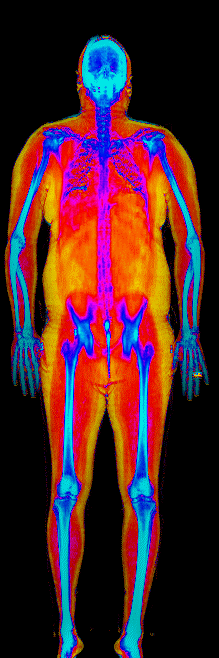

This page features real, anonymized DEXA scan images from BodyStats clients, organized by gender and body fat percentage in 5% increments. DEXA (Dual-Energy X-ray Absorptiometry) is the clinical gold standard for measuring body composition — far more accurate than scales, calipers, or visual estimates.

Each colorized scan shows the distribution of fat tissue (shown in warmer colors) and lean tissue (cooler colors) throughout the body. Compare your own DEXA scan to others in your range, or see what different body fat levels actually look like on a scan.

Female DEXA Scans by Body Fat %

30 to 35% body fat